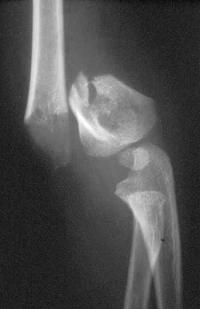

Radiographie

On demande une radiographie du coude Face et Profil

Le trait est transversal, extra-articulaire.

En fonction de l’importance du déplacement, on détermine le type de la fracture (classification de Lagrange et Rigault) :

- Stade 3 : bascule importante mais les 2 fragments restent en contact

- Stade 4 : bascule importante, les 2 fragments ont perdu tout contact

Traitement chirurgical

Brochage percutané

C’est l’embrochage externe selon Judet.

Il consiste, sous anesthésie générale, après réduction, à stabiliser la fracture par 2 broches introduites en externe en percutané.